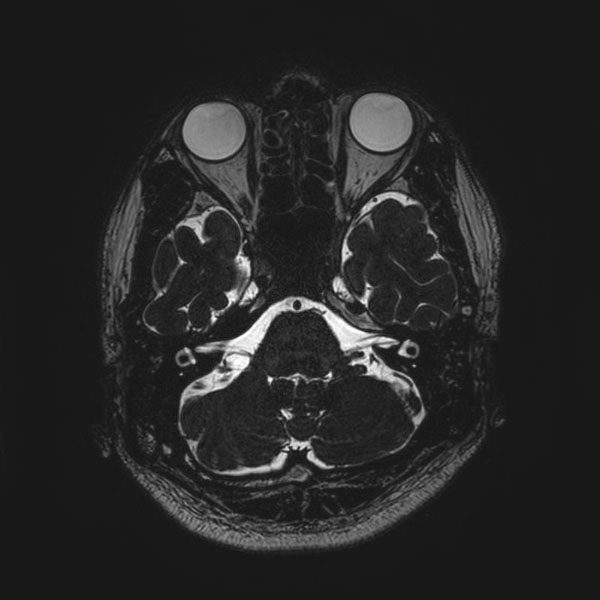

手術前

(MR1)